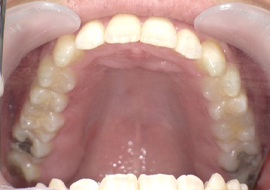

症例5

Before

After

| 主訴 | 上下3-3の並びが気になる |

|---|---|

| 年齢 | --- |

| 治療 期間 |

約1年 |

| 治療 内容 |

インビザライン5-5 |

| 治療費 | ¥517,000(税込)/調整料含む |

| 治療のリスク | 奥歯を動かさないので、前に出して並べていく。 歯と歯が移動するスペースを作るので、知覚過敏の症状がまれにでる。 歯を動かすことで、歯茎が下がるリスクある。 矯正終了後は、リテーナーを使用し、後戻りを防ぐ必要がある。 |